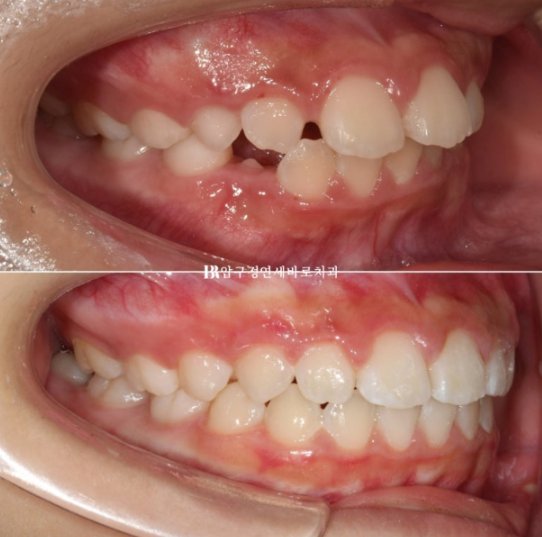

전 후 비교 보겠습니다.

치료 기간은 1년 2개월입니다.

23.10~24.12

뻗쳐있던 앞니 각도가 개선이 되면서 돌출이 해소가 되었습니다.

앞니 돌출이 해소가 되니 개선된 미소 심미

돌출이 해소가 되니 입이 좀 더 편하게 다물립니다.

입술돌출과 호두턱도 개선이 되었습니다.